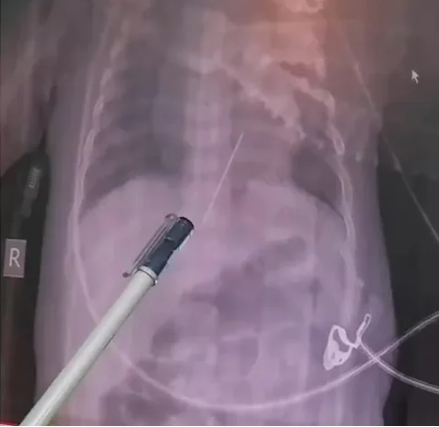

Eine Röntgenaufnahme enthüllte das Unglaubliche – eine vier Zentimeter lange Nadel hatte sich im Herzen des kleinen Mädchens verfangen.

Eine Röntgenaufnahme enthüllte das Unglaubliche – eine vier Zentimeter lange Nadel hatte sich im Herzen des kleinen Mädchens verfangen. Diese scharfe Nadel hatte sich offenbar einen gefährlichen Weg durch den Magen des Babys gebahnt und war im linken Ventrikel stecken geblieben, der lebenswichtigen Herzkammer, die den Körper mit Sauerstoff versorgt.

Sofort wurde das Baby in den Operationssaal geschoben, wo ein Team von Ärzten in einer Notoperation die Nadel aus dem Herzen des Babys entfernen konnte. Die Ärzte sind über die erfolgreiche Operation erleichtert und optimistisch bezüglich der Genesung des Babys, das nun auf der Intensivstation unter Beobachtung liegt.